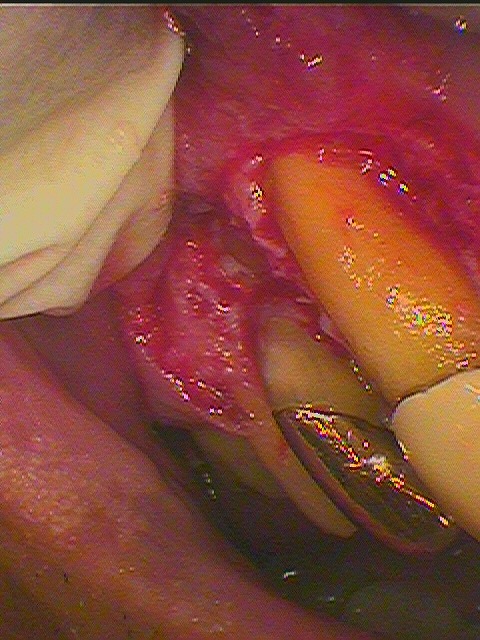

開けてみました3番にも根尖近くまで歯石が存在しています

頬側根は完全に骨には埋まっていないです

頬側根を抜歯してCRにて逆根充しています

綺麗にして閉じています